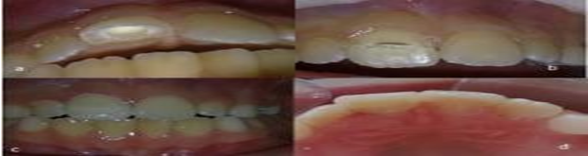

- Diş travmalarının tedavisi